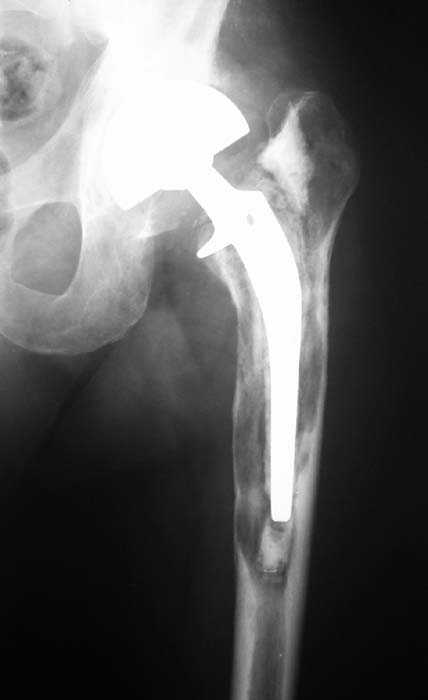

Мужчина, 39 лет.По поводу двустороннего асептического некроза головок бедренных костей последовательно выполнено тотальное эндопроезирование левого (1998 г), затем правого (1999 г) тазобедренных суставов.

С 2001 г отмечает нарастающие боли в левом бедре. Предполагается удаление протеза, удаление цемена из канала бедра, пластика дефекта бедренной кости.

Нет никакого смысла делать операцию в два этапа. С чашкой все понятно - стандартный подход с установкой пресс-фит компонента. На бедре имеет

место перипротезный перелом В3 типа - т.е. перелом вокруг ножки с ее нестабильностью на фоне выраженного остеолиза. Решение - доступ к каналу

через перелом с удалением самой ножки, костного цемента и рубцовых тканей. Установка ножки дистальной фиксации (типа Solution), длину ножки

надо определить по шаблону. Минимальный контакт ножки с интактной костью - 6-8 см. Фрагменты проксмального отдела собираются на ножке

эндопротеза, дефекты костной ткани заполняются чипсами (аллографт) и фиксируются кортикальными аллографтами, уложенными дополнительно по типу

"вязанки хвороста" серкляжом. Мы имеем 8 или 10 подобных наблюдений и результатами довольны.